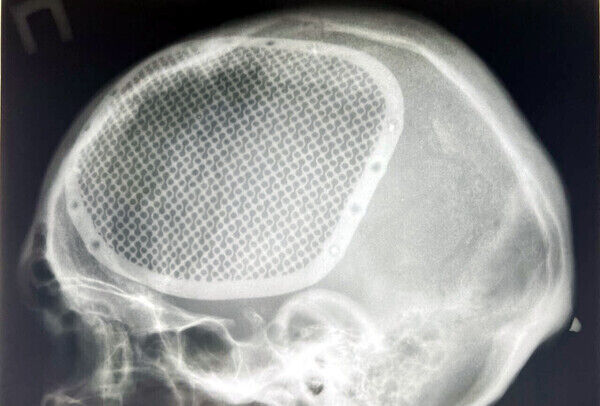

- Ein Soldat erlitt im Januar 2024 bei einer Minenexplosion eine schwere Schädelverletzung. Nach mehreren Monaten der Stabilisierung im Krankenhaus konnte ein maßgeschneidertes Schädelimplantat entwickelt und eingesetzt werden. Die Operation verlief erfolgreich, und der Patient hat gute Genesungschancen.